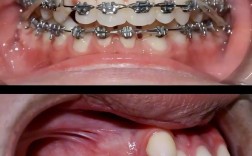

传统金属托槽矫正是应用最广泛的方法,通过将金属托槽用黏合剂固定在牙齿表面,再利用弓丝与托槽的连接,施加持续轻力引导牙齿移动,该方法矫治力稳定,适用范围广,无论是简单拥挤还是复杂错颌畸形均能有效解决,但缺点是美观性较差,托槽易刮伤口腔黏膜,且口腔清洁难度较大,需特别注意避免食用过硬、黏性食物。

自锁托槽矫正是在传统托槽基础上升级的技术,托槽自带闭锁装置,无需结扎丝或橡皮圈固定弓丝,减少了弓丝与托槽的摩擦力,这一优势使得牙齿移动更高效,可缩短矫治疗程(通常比传统方法缩短3-6个月),同时复诊间隔可适当延长,患者不适感也相对较轻,其费用较传统托槽高20%-30%,且对医生操作技术要求更高。